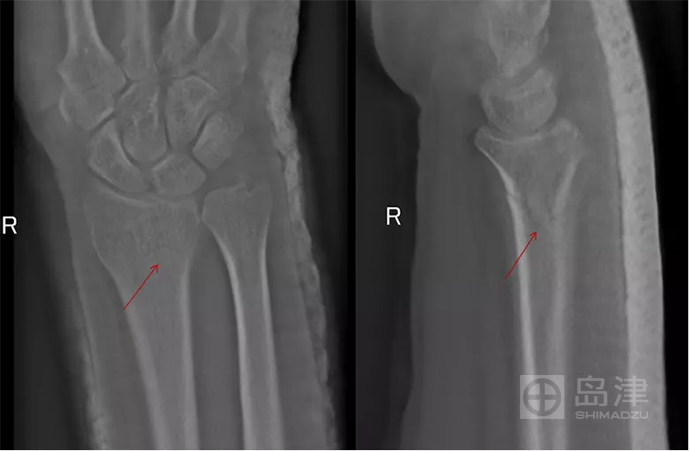

病例四:异物成像

女性, 50岁 ,右桡骨远端骨折后石膏固定,要观察骨折对位对线情况。无法拆除石膏,X线平片上高密度的石膏遮掩了骨折征象的显示。

DTS 检查避免了异物遮掩的影响,可以清晰观察骨折线及愈合情况。

异物干扰,DR无法显示

DTS骨折线清晰可见

图像来源:西安市第九医院